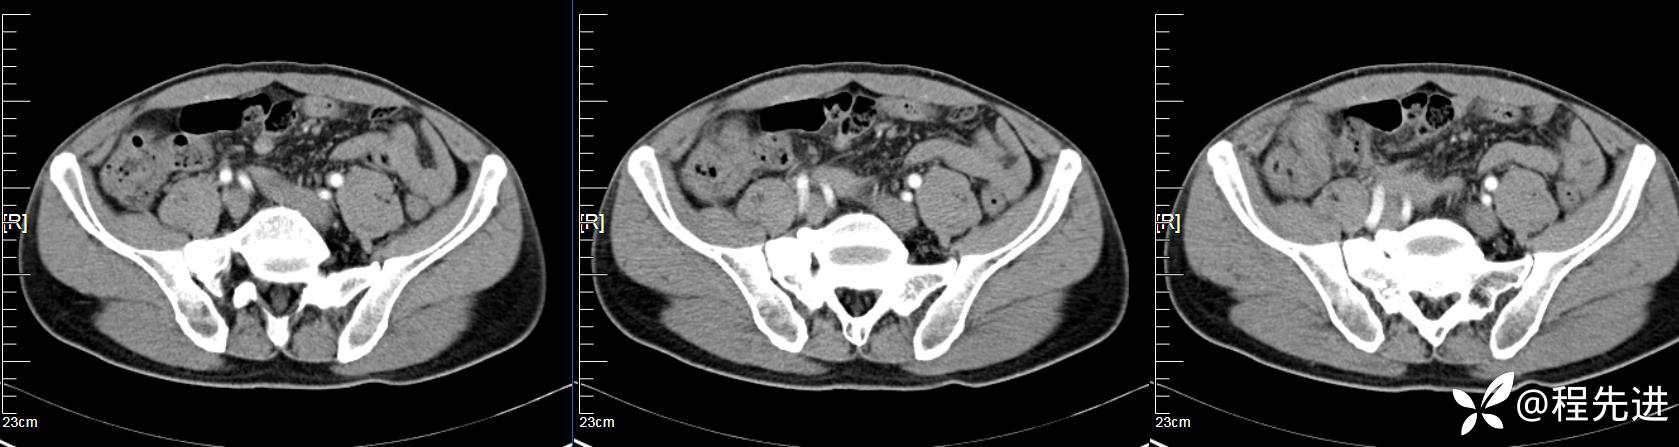

【患者信息】:男,61岁

【现病史及既往史】:右下腹部疼痛伴腹胀2天

【影像检查】